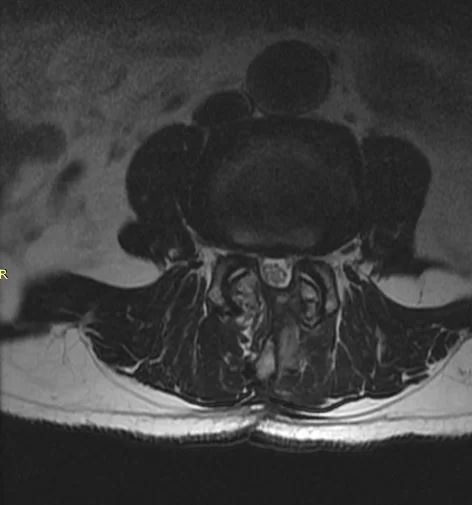

Η σπονδυλική στένωση είναι μια στένωση του καναλιού της σπονδυλικής στήλης, η οποία μπορεί να ασκήσει πίεση στα νευρικά στοιχεία της σπονδυλικής στήλης (Εικόνα 2). Η σπονδυλική στένωση εμφανίζεται συχνότερα στην οσφύ (μέση) και στον αυχένα.

Η διάγνωση συνήθως μπαίνει με την αξονική τομογραφία και τη μαγνητική τομογραφία. Η αξονική τομογραφία δείχνει πολύ καλά την ποιότητα των οστών ενώ η μαγνητική τομογραφία δείχνει εξαιρετικά ποιά νευρικά στοιχεία πιέζονται και βοηθά στην σωστή εκτίμηση της στένωσης (Εικόνα 3). Η μαγνητική τομογραφία είναι η πιό σημαντική εξέταση σ’ αυτή την περίπτωση.